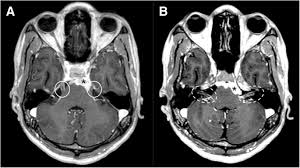

- MRI of the brain and spinal cord (with contrast)